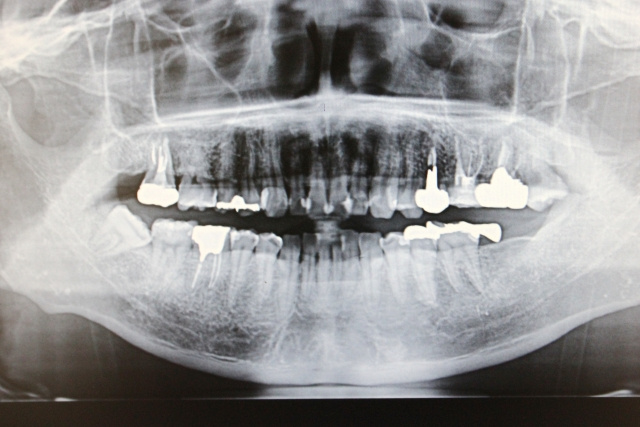

精度の高い矯正治療を行うためには、一般の歯科治療では使用しない特殊な医療機器が必要になります。

2Dレントゲンや口腔内カメラ(光学スキャナ)だけで検査を行う医院もあるようですが、歯を安全に移動させるためには、土台となる顎の骨の大きさや頭部骨格とのバランスなどを踏まえて治療計画を検討する必要があります。当院では歯科用CT、頭部規格写真まで撮影し、安全な治療計画をご提案できるよう努めています。